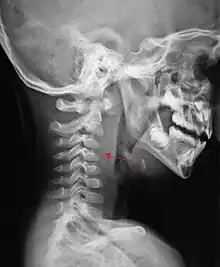

The retropharyngeal space (abbreviated as "RPS"[1][2]) is a potential space[2][3] and deep compartment of the head and neck[1] situated posterior to the pharynx.[4] The RPS is bounded anteriorly by the buccopharyngeal fascia, posteriorly by the alar fascia, and laterally by the carotid sheath. It extends between the base of the skull superiorly, and the mediastinum inferiorly.[1] It contains the retropharyngeal lymph nodes.[2] Its function is to facilitate movements in the superoinferior axis of the larynx, pharynx, and esophagus in relation to the cervical spine.[3]

If more than half of the size of the C2 vertebra, it may indicate retropharyngeal abscess.[7]